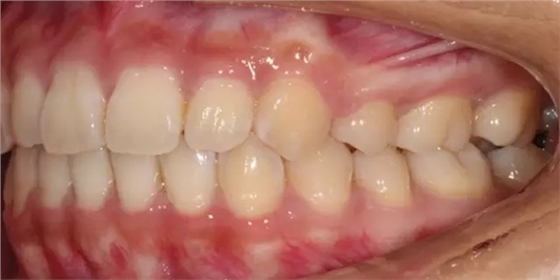

患者側(cè)面凸,鼻唇角較銳,笑時(shí)露齦笑明顯上下牙列擁擠,磨牙尖牙Ⅱ 類關(guān)系,3 度的深覆牙合,上頜中切牙伸長內(nèi)傾拔除上頜雙側(cè)的第一前磨牙,先粘上頜高轉(zhuǎn)矩的自鎖托槽排齊牙列,唇向開展上頜切牙,有一定的覆蓋,粘下頜標(biāo)準(zhǔn)轉(zhuǎn)矩托槽,上頜 1, 2 之間植入種植支抗壓入,同時(shí)后牙 5, 6 之間植入種植支抗內(nèi)收前牙,打開咬合關(guān)閉間隙。治療關(guān)鍵:前牙轉(zhuǎn)矩的控制第 1 個(gè)月 上頜粘上 Damon Q 高轉(zhuǎn)矩托槽,上 .014 熱激活 NiTi 絲。第 3 個(gè)月 上換 .014 x .025 熱激活 NiTi 絲。第 5 個(gè)月 上頜基本排齊,覆蓋增大,上換 .017 x .025 NiTi絲,下頜粘托槽,下 .014 熱激活 NiTi 絲。第 7 個(gè)月 上 .017 x .025 NiTi 絲加搖椅,下?lián)Q .014 x .025 熱激活 NiTi 絲第 9 個(gè)月 上頜換 .019 x .025 NiTi 絲加搖椅,下頜換 .017 x .025 NiTi 絲第 11 個(gè)月 下頜換 .019 x .025 加搖椅,上頜 1, 2 之間, 5, 6 之間植入種植釘,下頜出現(xiàn)散隙。第 13 個(gè)月 上頜換 .019 x .025ss 加搖椅,前牙種植釘用 Power Chain 壓低前牙(每側(cè) 100g),后牙種植釘關(guān)閉間隙(每側(cè) 150g),下?lián)Q .019 x .025ss,Power Chain 關(guān)閉間隙。第 19 個(gè)月 上頜前牙基本壓低到位去除前牙種植釘,繼續(xù)用關(guān)閉間隙,下頜散隙關(guān)閉。

第 22 個(gè)月 上頜覆蓋變小,去除 5, 6 之間種植釘,后牙前移關(guān)閉間隙。第 30 個(gè)月 患者未配合中線牽引,下中線仍有 1mm 右偏,患者對矯治效果滿意要求拆除,拆除固定矯治器,取模制作壓模保持器。 1.骨性 Ⅱ 類的患者內(nèi)收前牙時(shí)需對上頜前牙的轉(zhuǎn)矩進(jìn)行較好的控制才能獲得良好的面型和唇部形態(tài)。 2.露齦笑的患者治療前要分析其病因是唇、牙齦、牙齒、牙槽骨、上頜骨或多種因素結(jié)合,再制定矯治方案。 3.Ⅱ 類第二分類伴露齦笑的患者的上頜前牙移動軌跡是唇向開展-壓低-整體內(nèi)收。 4.Ⅱ 類第二分類牙齒舌傾比較厲害的情況,上頜中切牙慎用樹脂咬合墊。 5.壓低前牙或控根移動時(shí)容易發(fā)生牙根的吸收,需輕力緩慢的移動。